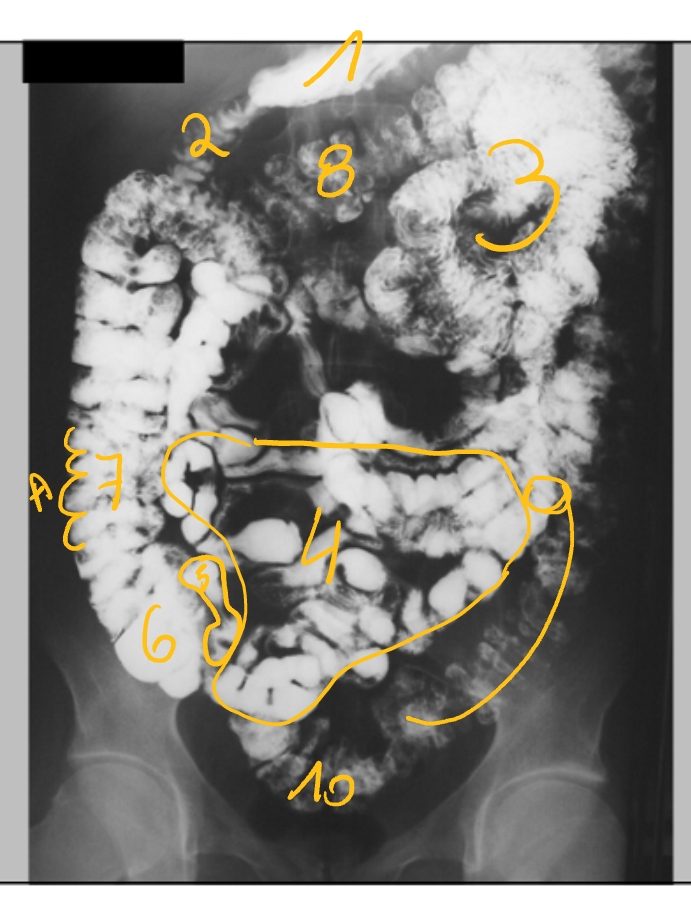

(transit-onderzoek)

maag

duodenum, pars descendens

jejunum

ileum

laatste ileale lis

caecum

colon ascendens

→ A: haustra’s (lopen niet door)

colon transversum

colon descendens

colon sigmoideum

(in rechter fossa)

→ gaat over in colon

→ tussen beide: klep van Bauhin

plicae circulares

bulbus duodeni

pars transversa duodeni

pars ascendens duodeni

hoek van Treitz

(= overgang van pars ascendens duodeni naar jejunum)

(dubbelcontrast → bariumsulfaat + lucht)